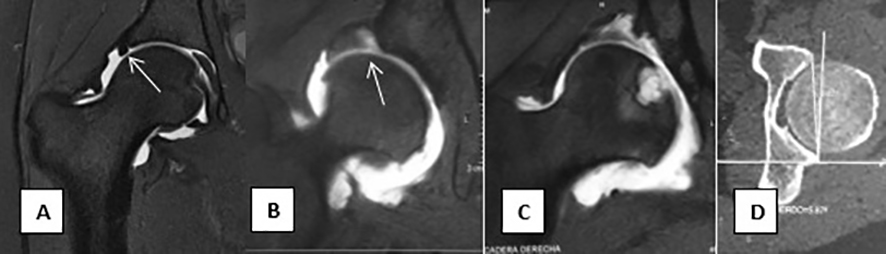

Figura 2

A- cadera sana, labrum de tamaño y estructura normal (flecha).

B- cadera displásica subluxada, afinamiento superior del cartílago articular, labrum hipertrófico y desinsertado (flecha).

C- Cadera displásica y subluxada, degeneración intrasubstancia del labrum, edema óseo y geodas.

D- TAC con anteversión acetabular de 5,8° (fisiologicamente retroverso).

Se realizó una artro-RM en 6 caderas y una RM en 8 para evaluar el labrum, el cartílago articular y las partes blandas (Figura 2). A un paciente diagnosticado de acetábulo retroverso se le realizó una TC para medir la anteversión acetabular (Figura 2).

Utilizamos la Rx antero-posterior y lateral de pelvis y caderas, una radiografia de falso perfil para observar el borde anterior del acetábulo y medir el ángulo centro borde anterior o de Lequesne (>20°), radiografía en abducción, fundamental en el paciente candidato a una PAO, ya que simula la rotación acetabular, por lo que sirve para evaluar si la cabeza femoral permanecerá concéntrica, sin efecto bisagra superior. La Artro-RM para evaluar las partes blandas, como el tendón del m. psoas, los músculos glúteos, la bursa trocantérica, el labrum, el estado del cartílago articular y la irrigación de la cabeza femoral (Figura 2). T1 sirve mejor para observar estas estructuras anatómicas, mientras que T2 es más útil para identificar lesiones, ya que es más sensible a la presencia de edema e inflamación. La artro-resonancia mejora la sensibilidad y especificidad y es el estudio de elección para definir la gravedad de la lesión del labrum, del cartílago articular, los gangliones, e incluso de la lesión cam (es el único estudio que permite analizar correctamente la zona antero lateral del offset cabeza cuello) y, por último, la TAC.